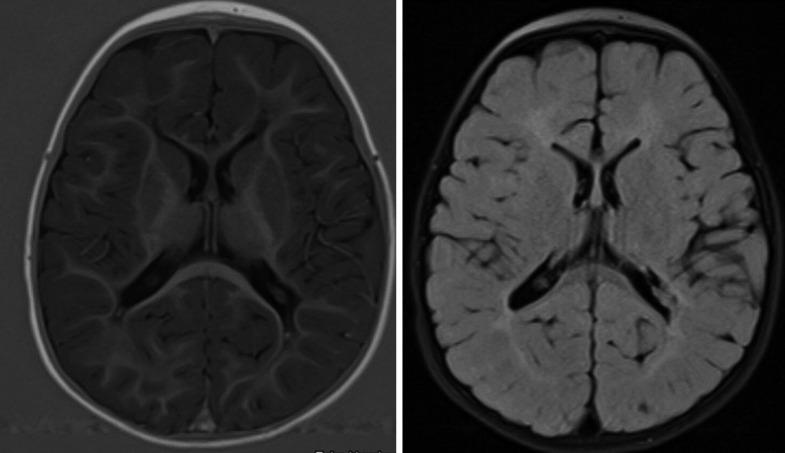

We present a case of a former late preterm male with hypoplastic left heart syndrome and history of hypoxic ischemic encephalopathy, who was diagnosed with spastic diplegic cerebral palsy in the setting of periventricular leukomalacia. Like many children with critical CHD, this child had gross motor delays and tone abnormalities in infancy. However, unlike many children with CHD, he continued to have neurologic differences that prompted additional evaluation through a Cardiac Neurodevelopmental Program. He was diagnosed with spastic diplegic cerebral palsy based upon clinical history and physical examination. Ancillary testing showed periventricular leukomalacia on brain magnetic resonance imaging (MRI); this finding was consistent with his clinical diagnosis.

我们报告一例 former late preterm 男性患儿,患有左心发育不全综合征且有缺氧缺血性脑病病史,在脑室周围白质软化的情况下被诊断为痉挛性双瘫型脑瘫。和许多患有严重CHD的儿童一样,该患儿在婴儿期有粗大运动发育迟缓及肌张力异常。然而,与许多CHD患儿不同的是,他持续存在神经方面的差异,促使通过心脏神经发育项目进行进一步评估。根据临床病史和体格检查,他被诊断为痉挛性双瘫型脑瘫。辅助检查显示脑磁共振成像(MRI)有脑室周围白质软化;这一发现与他的临床诊断相符。